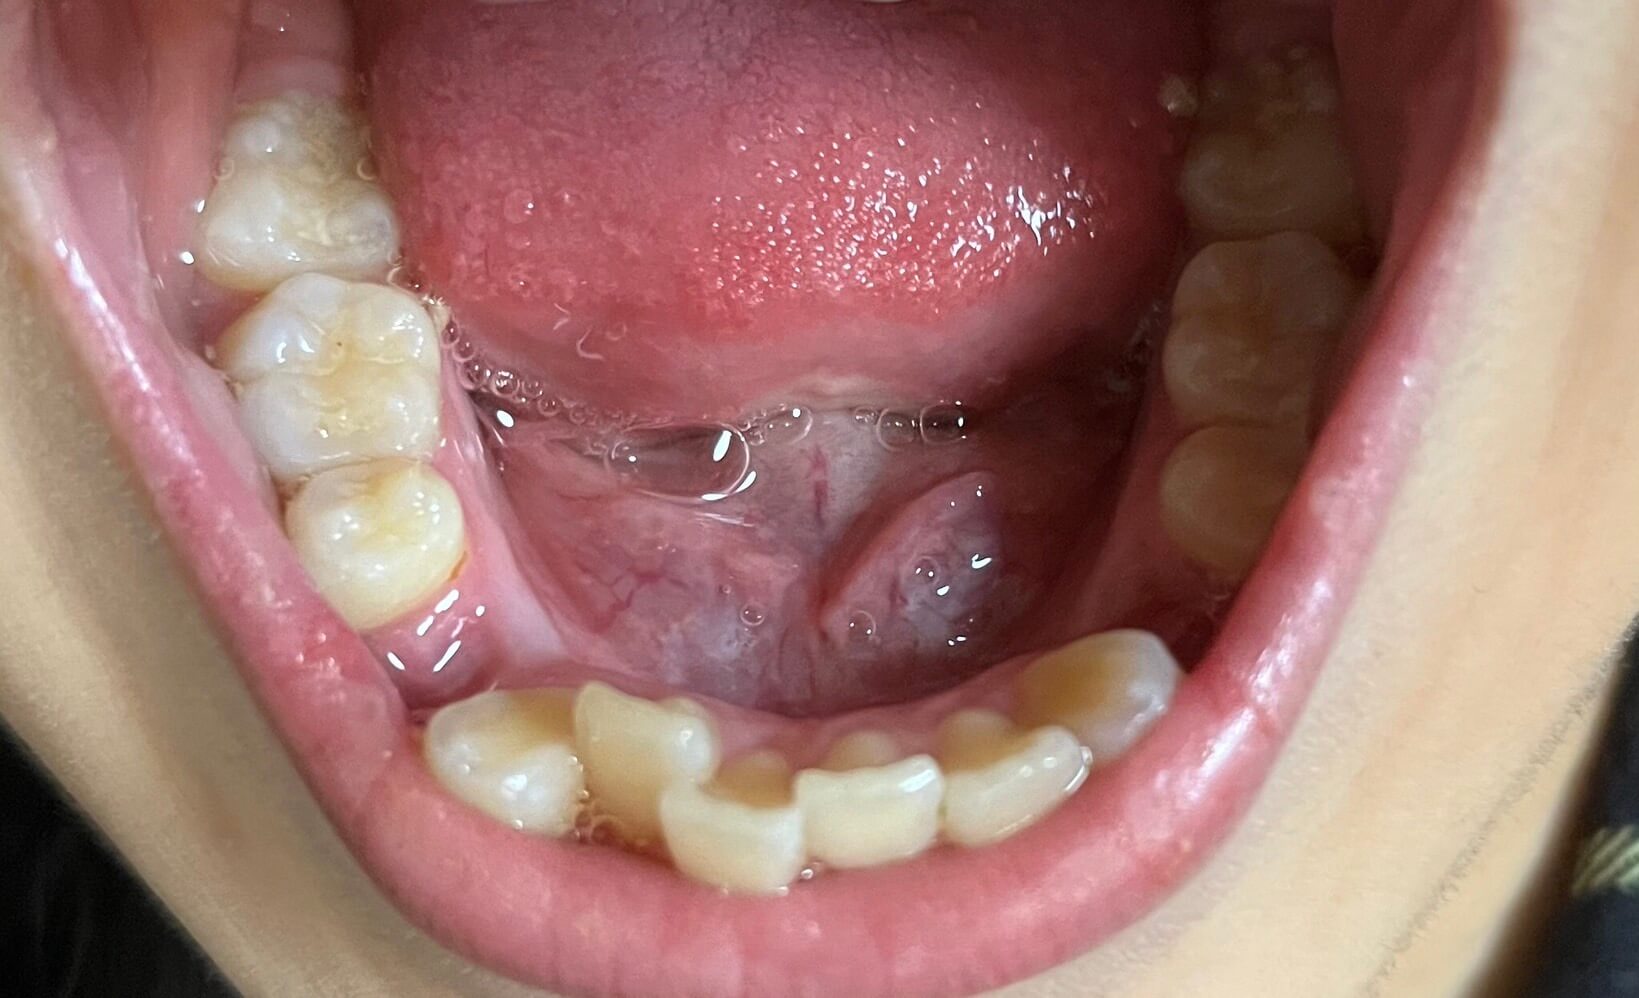

| 年齢・性別 | 21歳 |

|---|---|

| 主訴 | 叢生が気になる・前歯に埋伏歯がある |

| 治療期間・回数 | 6ヶ月 |

| 費用 | 935,000円 |

| 上顎の左側3番が埋伏していたため、上顎左右の3番および親知らずを抜歯し、矯正治療を行いました。 治療開始からおよそ6ヶ月で歯列が整い、審美的にも機能的にも良好な結果が得られた症例です。 |